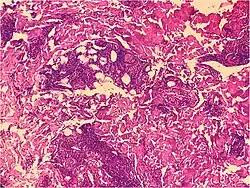

Kaposi’s sarcoma in patch stage The patch stage typically shows irregular proliferation of jagged vascular channels in the dermis below an integral epidermis. The so-called promontory sign is sometimes found in patch stage lesions and denotes vascular spaces surrounding pre-existing blood (see image).[23]

vessels